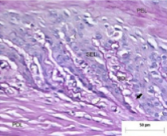

What does this show

Lamellar interdigitations